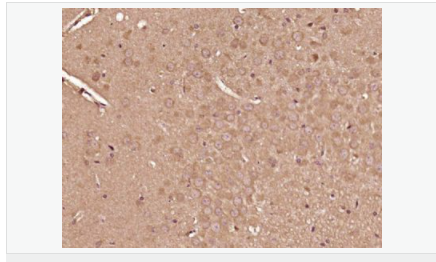

胰島素受體底物-2抗體

Rabbit anti-IRS-2 Polyclonal antibody

英文名稱(chēng)IRS-2

中文名稱(chēng)胰島素受體底物-2抗體

別    名Insulin Receptor Substrate 2; IRS 2; IRS-2; IRS2; IRS2_HUMAN.

研究領(lǐng)域細(xì)胞生物  神經(jīng)生物學(xué)  信號(hào)轉(zhuǎn)導(dǎo)  細(xì)胞凋亡  細(xì)胞膜受體  糖尿病

抗體來(lái)源Rabbit

克隆類(lèi)型Polyclonal

交叉反應(yīng)Human, Rat,  (predicted: Mouse, Horse, )

產(chǎn)品應(yīng)用ELISA=1:5000-10000 IHC-P=1:100-500 IHC-F=1:100-500 Flow-Cyt=1μg/Test ICC=1:100-500 IF=1:100-500 (石蠟切片需做抗原修復(fù))

免 疫 原KLH conjugated synthetic peptide derived from human IRS-2:461-560/1338

產(chǎn)品介紹This gene encodes the insulin receptor substrate 2, a cytoplasmic signaling molecule that mediates effects of insulin, insulin-like growth factor 1, and other cytokines by acting as a molecular adaptor between diverse receptor tyrosine kinases and downstream effectors. The product of this gene is phosphorylated by the insulin receptor tyrosine kinase upon receptor stimulation, as well as by an interleukin 4 receptor-associated kinase in response to IL4 treatment. [provided by RefSeq, Jul 2008]

IRS-2是肝胰島素信號(hào)轉(zhuǎn)導(dǎo)核心介子,IRS-2基因的缺失或IRS-2信號(hào)網(wǎng)絡(luò)上一些關(guān)鍵信號(hào)分子的異常改變,都將導(dǎo)致肝胰島素信號(hào)轉(zhuǎn)導(dǎo)能力減弱,出現(xiàn)肝胰島素抵抗.